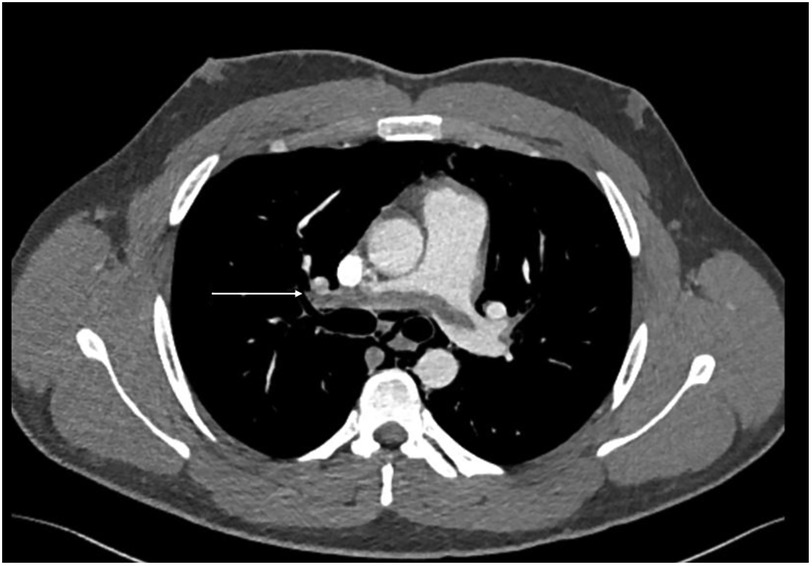

During acute coronary syndrome (ACS) exclusion workouts, transthoracic echocardiography images were very difficult to obtain, as hyperechoic moving artifacts were interfering with the ultrasound probe. Immediate chest x-ray showed massive pneumomediastinum (Figure 1). A subsequent CT scan confirmed the massive pneumomediastinum (Figure 2) and revealed the presence of an acute bilateral pulmonary embolism (Figure 3). Laboratory tests showed elevated D-Dimer levels (2,515 ng/mL), polycythaemia (hemoglobin 18.9 g/dL, haematocrit 55.5%), and slightly elevated creatinine (1.48 mg/dL, creatinine clearance 49 mL/min) with mild hypoalbuminemia (3.2 g/dL).

Figure 1

Chest x-ray showing massive pneumomediastinum tracking up to the base of the neck. (a) subcutaneous emphysema (b) extra pleural air sign (c) the continuous diaphragm sign.